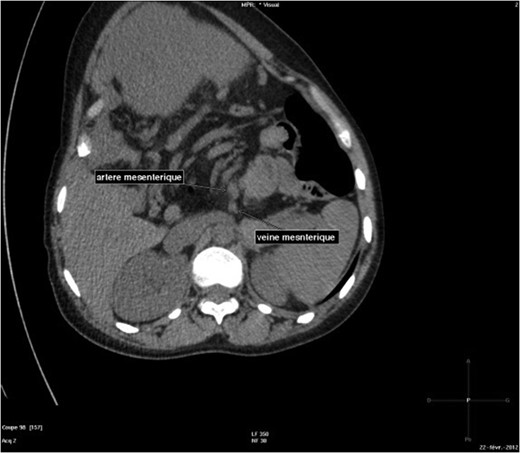

The abdominal-pelvic CT-scan showed a pre-splenic left position of the caecum and right colon, with no part of the colon on the right. The radiologist concluded that the patient was suffering from a complication of intestinal malrotation (IM) (Figs 1, 2, 3).

Abdominal-pelvic CT-scan, non-contrast enhanced, in the sagittal plane.